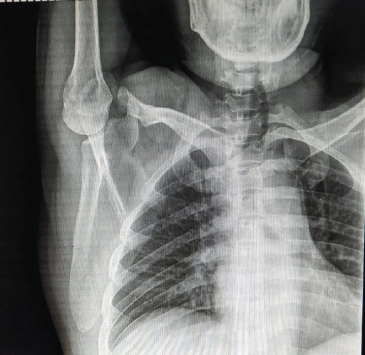

A Primary Hyperparathyroidism in an Adolescent Female with Pathological Fractures and Multiple Bone Lesions Due to Parathyroid Adenoma: Case Report

Harsh Pratap Singh , Chetan Singh , Kishore Parihar , Ankita Parmar , Sanavvar Ali , Anmol Chaurasia